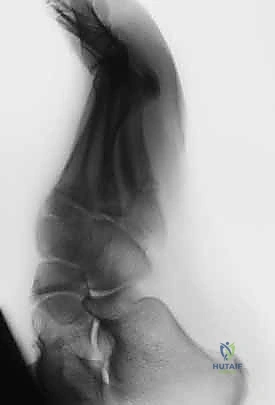

التشخيص الدقيق: خطوة حاسمة نحو العلاج الصحيح

التشخيص الخاطئ لكسر جونز (كاعتباره التواءً في الكاحل أو كسراً قلعياً بسيطاً) قد يؤدي إلى كوارث طبية تستمر لأشهر. يعتمد الأستاذ الدكتور محمد هطيف على بروتوكول تشخيصي صارم يضمن تحديد نوع الكسر بدقة متناهية.

- الفحص السريري الدقيق: يبدأ الدكتور هطيف بالاستماع لتاريخ الإصابة، ثم فحص القدم لتحديد نقاط الألم بدقة، وتقييم الدورة الدموية والأعصاب في القدم.

- التصوير بالأشعة السينية (X-rays): هي الخطوة الأولى والأساسية. يتم أخذ صور بأوضاع مختلفة (أمامية، جانبية، ومائلة) لتحديد موقع الكسر وشكله بدقة.

- التصوير بالرنين المغناطيسي (MRI) أو الأشعة المقطعية (CT Scan): في بعض الحالات المعقدة، أو إذا كان الكسر إجهادياً قديماً ولم يظهر بوضوح في الأشعة العادية، يطلب الدكتور هطيف هذه الفحوصات المتقدمة لتقييم مدى تلف العظم والأنسجة المحيطة.